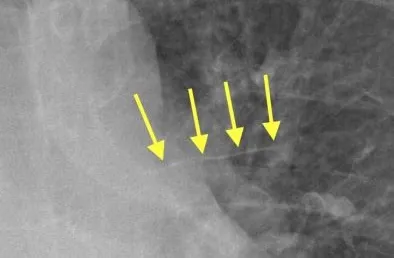

Thickening of interlobar fissures: Fluid between the lobes of the lung

<p><b>Thickening of interlobar fissures:</b> Fluid between the lobes of the lung